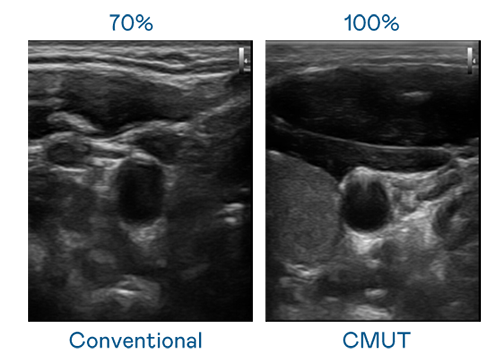

CMUT 技术是一种用电容式微机电元件来产生超音波讯号的技术。与传统 PZT 压电式技术相比,CMUT 频宽增加 30%,更宽频的超音波讯号让影像解析度大幅提升,是实现高影像品质医疗超音波扫描、促进精准医疗发展的关键技术。

超音波影像的解析度高低,首先取决于探头能发出的讯号频宽。问鼎28 CMUT 可提供高清晰的超音波讯号,提供高频宽、高灵敏度、影像纹理细节更高的超音波影像,协助医护人员缩短影像判读时间及利用精准的医疗影像进行诊断。